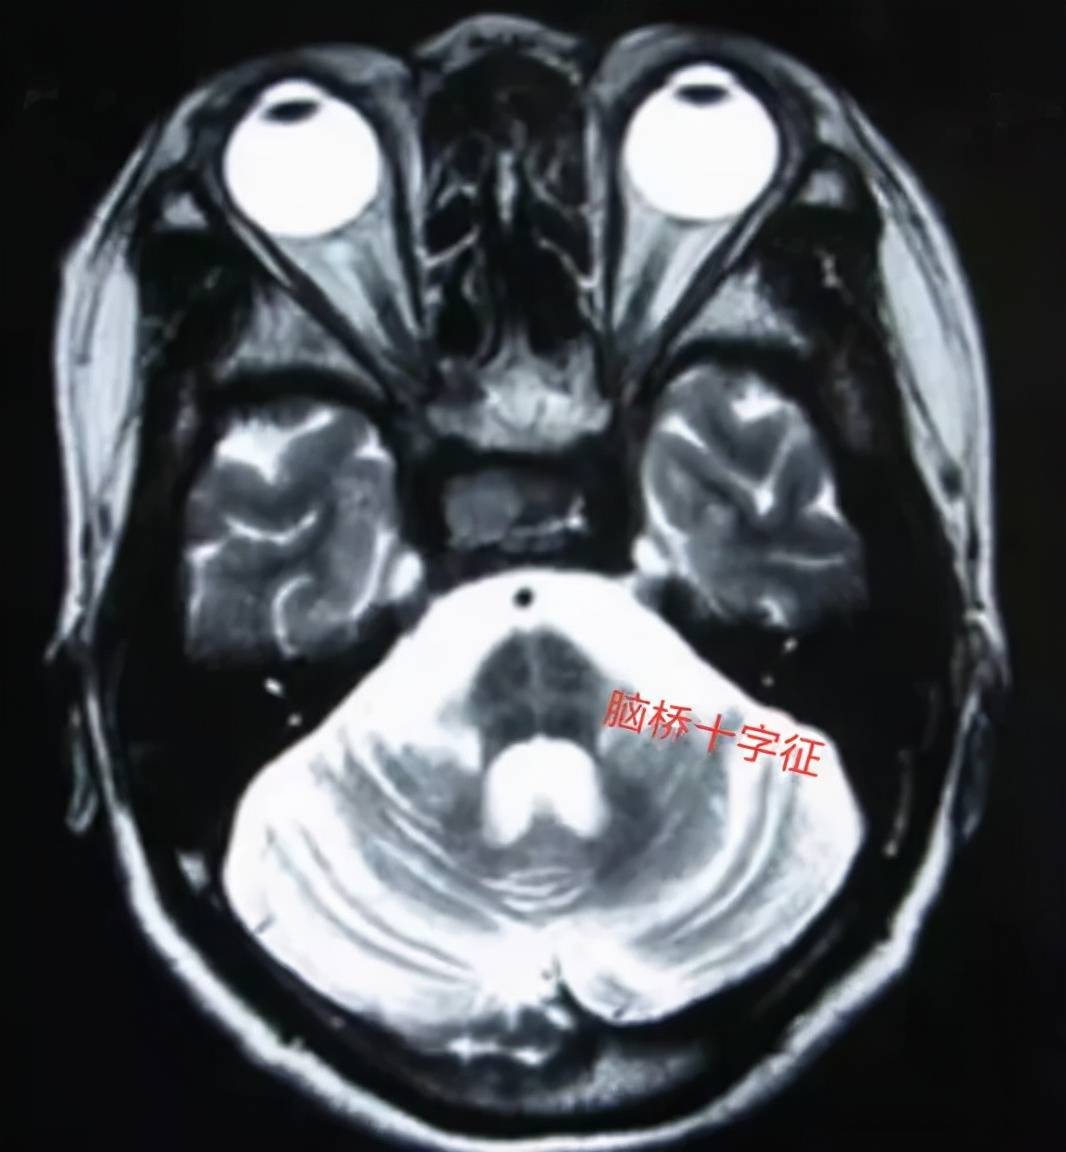

图 |核磁提示脑桥、小脑明显萎缩

⑥MRI核磁表现壳核、小脑中脚、脑桥或小脑萎缩;

【诊断|【小帕讲故事】诊断多系统萎缩1、2、3】②MRI核磁表现壳核、小脑中脚或脑桥萎缩;

③18F-FDG-PET表现为壳核、脑干或小脑低代谢 。